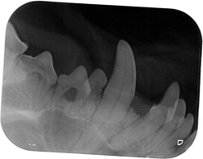

| Poor Cuba's xray |

The 'Bubble' dog has returned. Our darling fluff ball Cuba has earned this nickname after a string of expensive and obscure illnesses since birth – think chicken allergy, shoulder strain and almost losing an eye. One friend suggested we put her in a bubble to keep her safe.

Well, the next instalment in the Cuba chronicles has arrived. She has a shocking case of tonsillitis and today needed her tonsils removed. Yes, you read that correctly – our dog had its tonsils removed.

She is down a few teeth and two tonsils. We are down a big wad of cash. Today I am both grateful and smiling. I’m smiling because the adorable fluff ball is ok and grateful that we succumb to the embarrassment a few years and purchased pet insurance. Wise move!